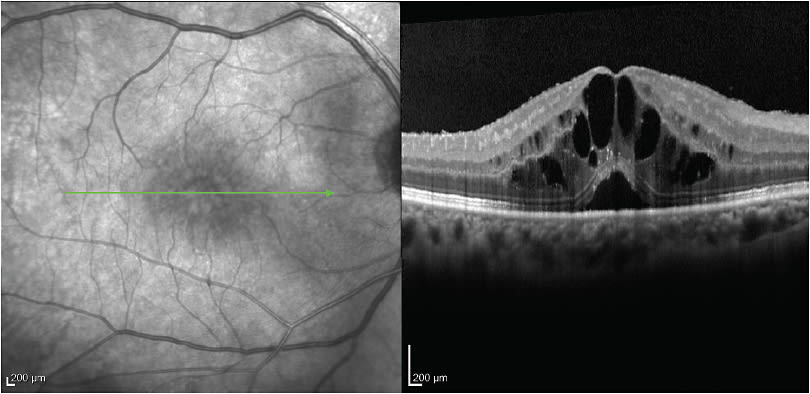

AGE-RELATED MACULAR DEGENERATION

Patients age 50 or older who present with symptoms of distortion or blurred vision require careful examination, as these complaints may be due to macular pathology secondary to age-related macular degeneration. AMD is a leading cause of blindness among Americans who are 65 years or older. OCT is vital in helping to identify drusen, geographic atrophy and ellipsoid zone disruption, indicating a possible choroidal neovascular membrane, as no other imaging device is capable of this (Figure 8).

Figure 8. Left: OCT of drusen. Right: OCT of subretinal fibrosis and subretinal fluid secondary to exudative age-related macular degeneration.

Patients whose eyes have symptoms of macular degeneration need additional imaging tests, such as fundus autofluorescence, to better highlight drusenoid change and geographic atrophy; they also need fluorescein and impedance cardiography (ICG) angiography to identify abnormalities of the blood-retinal barriers.

Earlier referral to a retinal specialist for AMD management may be helpful as the treatment regimen can be complex. To treat wet AMD, the surgeon must decide on whether to initiate anti-VEGF injections, as patient selection is crucial concerning which anti-VEGF agent is optimal, and then deciding on the interval of anti-VEGF injections. Moreover, the complexity of treating AMD lies in the pathophysiology of the breakdown of the blood-retinal barrier and the pharmacodynamics of available treatments. The result is that treatment of AMD is a continuously dynamic process: It requires close patient follow-up; often necessitates changing the type of anti-VEGF agent used; and altering the interval of injection therapy.